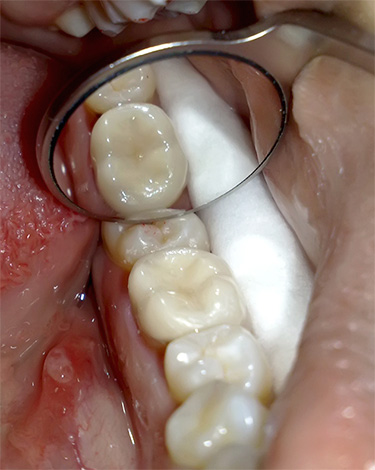

- Impostazione di un sigillo permanente da un composito fotopolimerizzabile o altro materiale importato (un esempio verrà mostrato nella foto sotto).

In diverse cliniche trattamento della pulite viene sempre eseguito in una sola visita e indipendentemente dal numero di canali: sono sigillati e viene immediatamente stabilito un riempimento permanente sul dente. Gli studi hanno dimostrato che spesso questa pratica porta a conseguenze negative a lungo termine, poiché il materiale introdotto nei canali deve prima indurirsi. Non iniziano i lavori di costruzione fino a quando la fondazione non si indurisce, poiché le conseguenze possono essere disastrose - e qui la situazione è la stessa. Questo è il motivo per cui si raccomanda di trattare la pulpite in almeno due visite.

L'uso di un microscopio, come intermediario tra un medico e il dente di un paziente, aumenta in modo significativo il prezzo già considerevole per il trattamento della pulpite di un dente a tre canali. Tuttavia, grazie a tale attrezzatura, il paziente può dimenticare per tutto il tempo che il trattamento è stato effettuato una volta nei canali del suo dente e dovrà solo andare dal dentista a volte per esaminare le condizioni del riempimento.